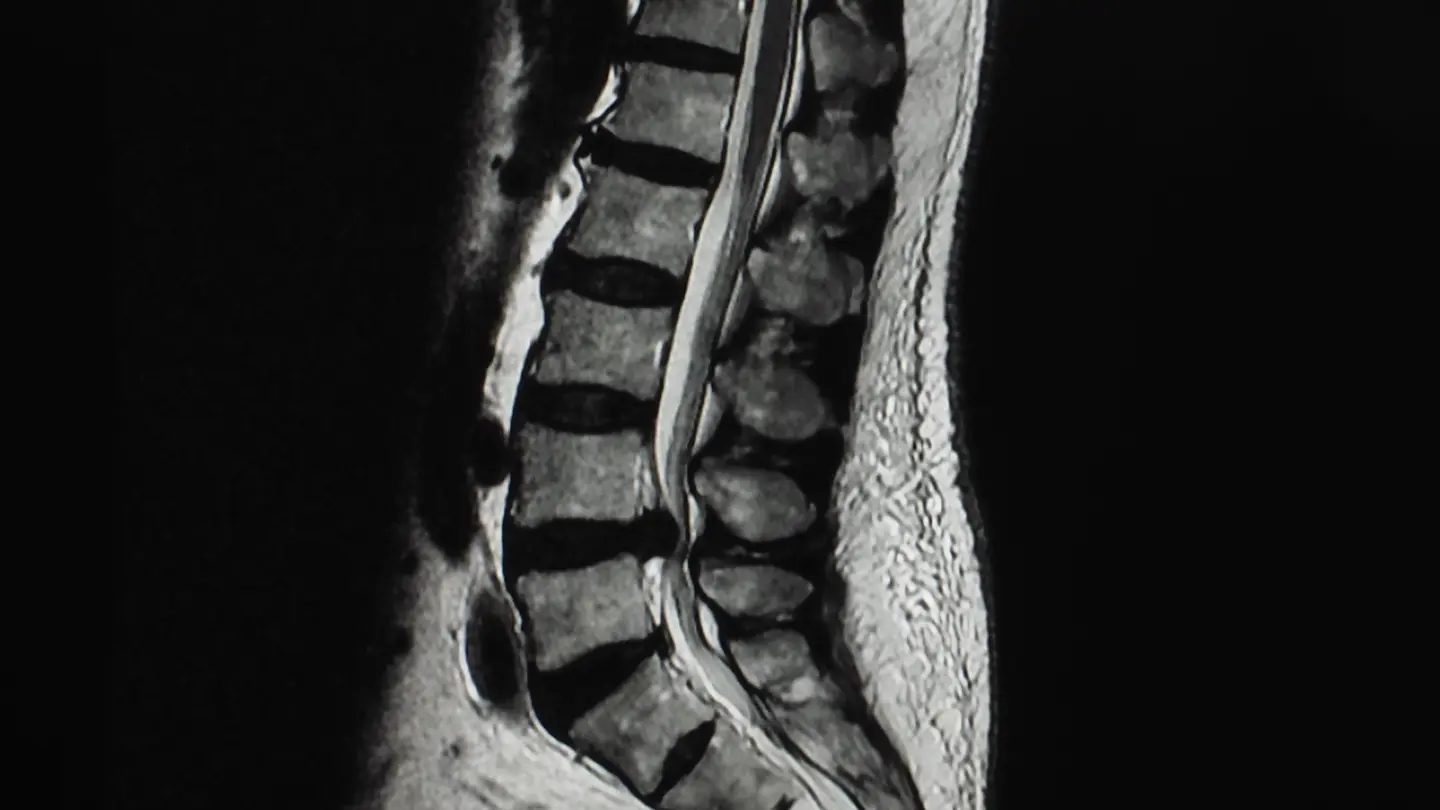

MRI Lumbar Spine L5 S1 Level

A spinal MRI scan can comprehensively assess the spine, including the lumbar, thoracic, and cervical regions, to identify any abnormalities or conditions affecting these areas.

A spine MRI scan can focus on one of three defined areas of the spine, depending on your symptoms and where you’re experiencing pain.

What can a spine MRI scan detect?

The results of your private MRI spine scan could help diagnose a range of injuries or conditions, including:

• Spinal fracture

• Improper spine curvature

• Inflammation

• Spinal cord damage

• Pinched nerves

• Spinal congenital defects

• Herniated discs

• Cervical stenosis

• Infections

• Tumours

A spine MRI scan is a diagnostic tool, so it won’t treat these conditions. However, the results will allow your physician to make informed decisions and recommend appropriate treatment.